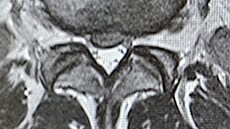

„Dostávám silné kapačky, užil jsem si svou oblíbenou magnetickou rezonanci během neděle a probíhá už i fyzioterapie. S léčbou jsem začal ve čtvrtek po návratu ze státní návštěvy v Bratislavě. Začátkem příštího týdne bych měl mít ještě jeden drobný zákrok, abych se vyhnul operaci, která časem asi bude nutná, ale rekonvalescence by nyní byla příliš dlouhá. Kdy budu z nemocnice propuštěn, to neumím odhadnout,“ vzkázal nám.